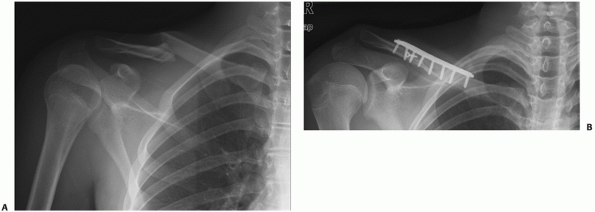

![]()  |

FIGURE 36-26 A.

Anteroposterior radiograph of a displaced distal clavicle fracture in a 38-year-old patient after falling off a mountain bike at high speed. Although the fracture was closed, there was significant bruising and swelling over the shoulder. The degree of displacement of this fracture suggests a high likelihood that delayed union or nonunion would result with nonoperative treatment. After the soft tissue swelling had subsided 10 days postinjury, operative fixation was performed with a plate specifically designed for the distal clavicle, allowing for the placement of four screws in the small distal fragment (B). The fracture healed uneventfully and the patient was able to return to work within a week of the surgery. C. Final follow-up radiograph following hardware removal for local soft tissue irritation, a common problem in this area, shows solid union.  |

goal (Fig. 36-26). Following fixation, the

surgeon must judge whether the number and quality of distal fragment

screws are sufficient to provide stability until union occurs. If this

is judged to be inadequate, there are several options at this point.

screws.49,52,182 This may be readily apparent during preoperative planning (Fig. 36-28)

or may only be realized intraoperatively. The advantage of subacromial